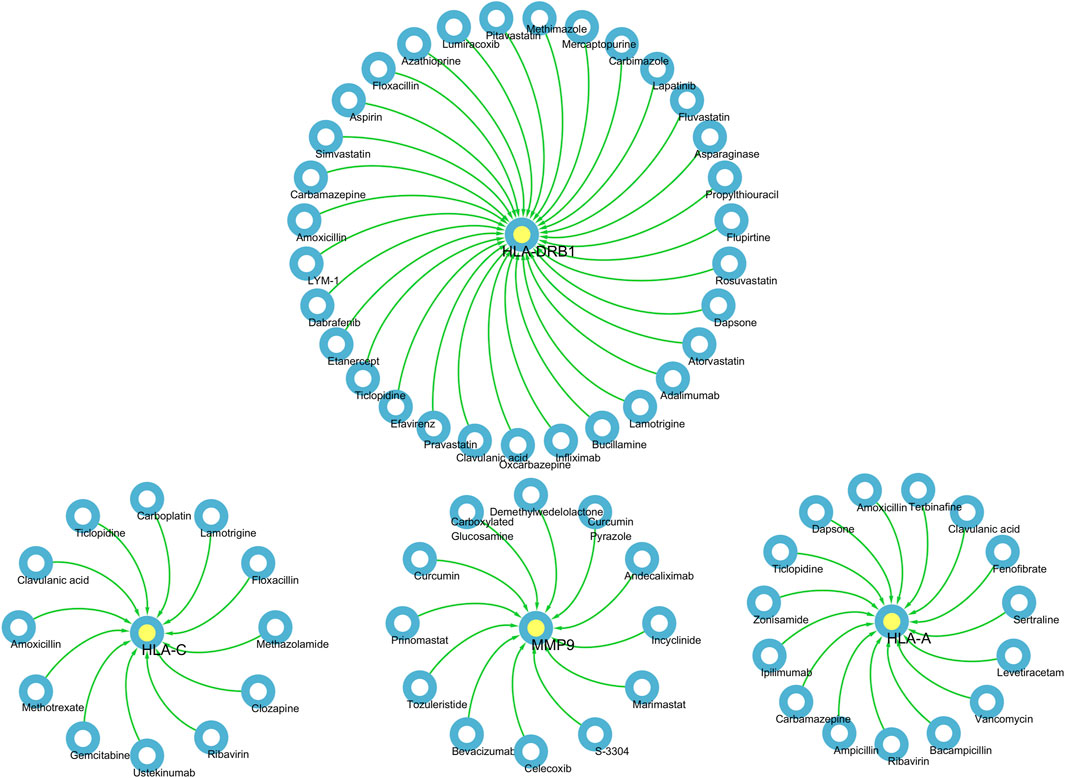

Pharmaco-transcriptomic analysisTo propose novel treatment strategies for Rifampicin-resistant spinal tuberculosis (TB), we performed a pharmaco-transcriptomic analysis using the Integration of the Drug–Gene Interaction Database (DGIdb 4.0). The DGIdb database (version 4.0) integrates information on drug-gene interactions and druggable genes sourced from publications, databases, and other web-based resources (Freshour et al., 2021). It serves as a comprehensive, publicly accessible web database. Finally, we utilized Cytoscape to assess and visualize the impact of drug molecule metabolism on the regulation of genes.

Pharmaco-transcriptomic analysisBased on the above results, HLA-A, HLA-C, HLA-DRB1, MMP9 and PLCL1 may be potential therapeutic targets for DSTB. Therefore, the results of our pharmaco-transcriptomic analysis can confirm that 13 drug compounds (e.g., Floxacillin, Clavulanic, and Amoxicillin) can regulate the expression of HLA-C. Similarly, there were 12 kinds of drug compounds found regulating MMP9, such as Celecoxib, Marimastat, and Andecaliximab. Moreover, 15 kinds of drug compounds (Terbinafine, Zonisamide, Ticlopidine, etc.) regulated the expression of HLA-A. In addition, Flupirtine, Fluvastatin, Methimazole, and other 18 drug compounds were confirmed to regulate the HLA-DRB1 (Figure 7). These experimental results will help us provide new insights into the treatment of DSTB.

Figure 7. We performed pharmaco-transcriptomics analysis by the results of key proteins for the PPI network.pharmaco-transcriptomic analysis used the Integration of the Drug–Gene Interaction Database (DGIdb 4.0).

Interestingly, HLA-DRB1, HLA-A and HLA-C were significantly increased in DSTB group, but MMP9 and PLCL1 were substantially decreased in DSTB group. The pharmaco-transcriptomic analysis identified various drugs (Floxacillin, Clavulanic, Ustekinumab and so on) capable of regulating the expression of these proteins. Ustekinumab, a human monoclonal antibody, was kown as a target inhibition of interleukin-12 and −23. Moreover, Morelli et al., 2022 demonstrated that interleukin-12/23 was related to HLA-C, since they preferentially present (auto) antigens, for example the metalloprotease (MMP) domain, to CD8 T cells. Our paper demonstrated that Ustekinumab could regulate the protein of HLA-C, which might be one of the mechanisms of Ustekinumab-induced upregulated risk of Rifampicin-resistant of spinal TB disease.